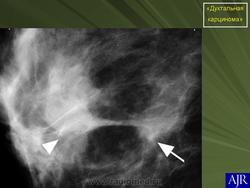

Инвазивная (или инфильтрирующая) протоковая карцинома – это наиболее часто встречающаяся форма рака молочной железы. Она составляет около 80 % из всех форм. В отличие от протоковой карциномы in situ, инвазивная карцинома характеризуется тем, что раковый процесс уже вышел за пределы молочного протока и распространяется на нормальные ткани молочной железы. Характерной особенностью инвазивной протоковой карциномы является очень твёрдая припухлость с неровными краями, которая спаяна с окружающим тканям. Сосок молочной железы или кожа вокруг него может быть втянута.

Часто на маммограммах в области опухоли выявляются микрокальцинаты, что связано с том, что в опухоли происходит омертвление ее клеток (некроз), которые в последствие пропитываются солями кальция. Опухоль при инвазивной карциноме может быть различных размеров, и у клеток может быть различное время деления, так что некоторые клетки растут быстрее других.